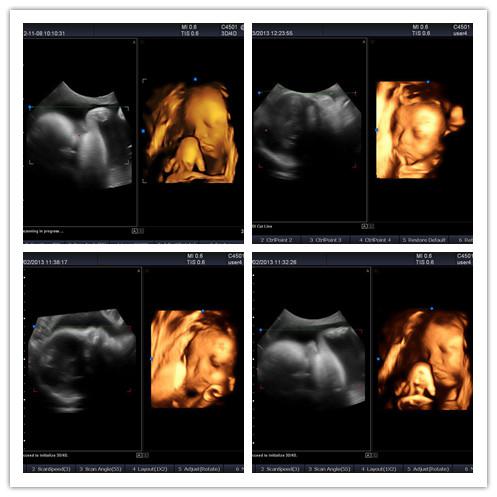

3、實時三維成像(4D) (選購)

通過SIUI自主研發的高質量實時三維容積探頭,輕松實現實時三維成像,方便、快捷、實時地顯示胎兒或臟器的立體信息。